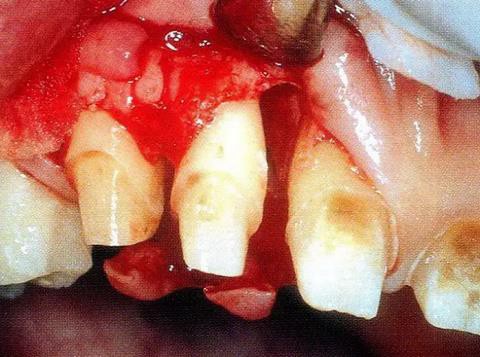

▼圖14-2 保存牙齦乳頭的同時進行了翻瓣形成,骨缺損部的廓清處理結(jié)束的狀態(tài)。骨缺損形態(tài)是從臨接面向腭側(cè)擴展開來的。